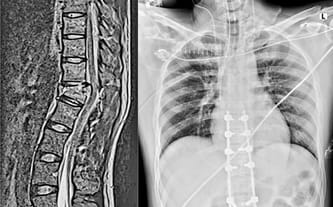

16 sierpnia 2023 roku to najgorszy dzień w naszym życiu. Właśnie wtedy Kacper spadł z wysokości około 5 metrów, doznał licznych złamań w obrębie kręgosłupa (złamanie kręgów Th10, Th12) wraz z porażeniem kończyn dolnych. Z energicznego, pełnego pasji mężczyzny stał się walczącym o życie i sprawność pacjentem jednego z lubelskich szpitali.

Z uwagi na doznanie licznych obrażeń ciała przeszedł wielogodzinną operację kręgosłupa. Przez kilka dni był utrzymywany w śpiączce i podłączony do respiratora. Miał problemy z oddychaniem, odmę płucną, liczne złamania żeber i mostka. Gdy jego stan się ustabilizował, mógł zostać przeniesiony do Kliniki Rehabilitacji, w której przebywa do dziś.